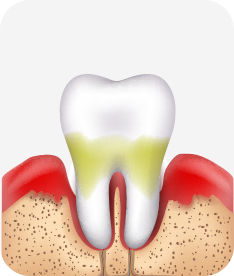

치은염 (초기~중기)

치아 주위의 잇몸이 붉게 부어 있으며, 칫솔질 등을 할 때 피가 남.

스케일링 주기의 조절이 필요할 수 있으며, 올바른 칫솔질을 시행하여야 함.